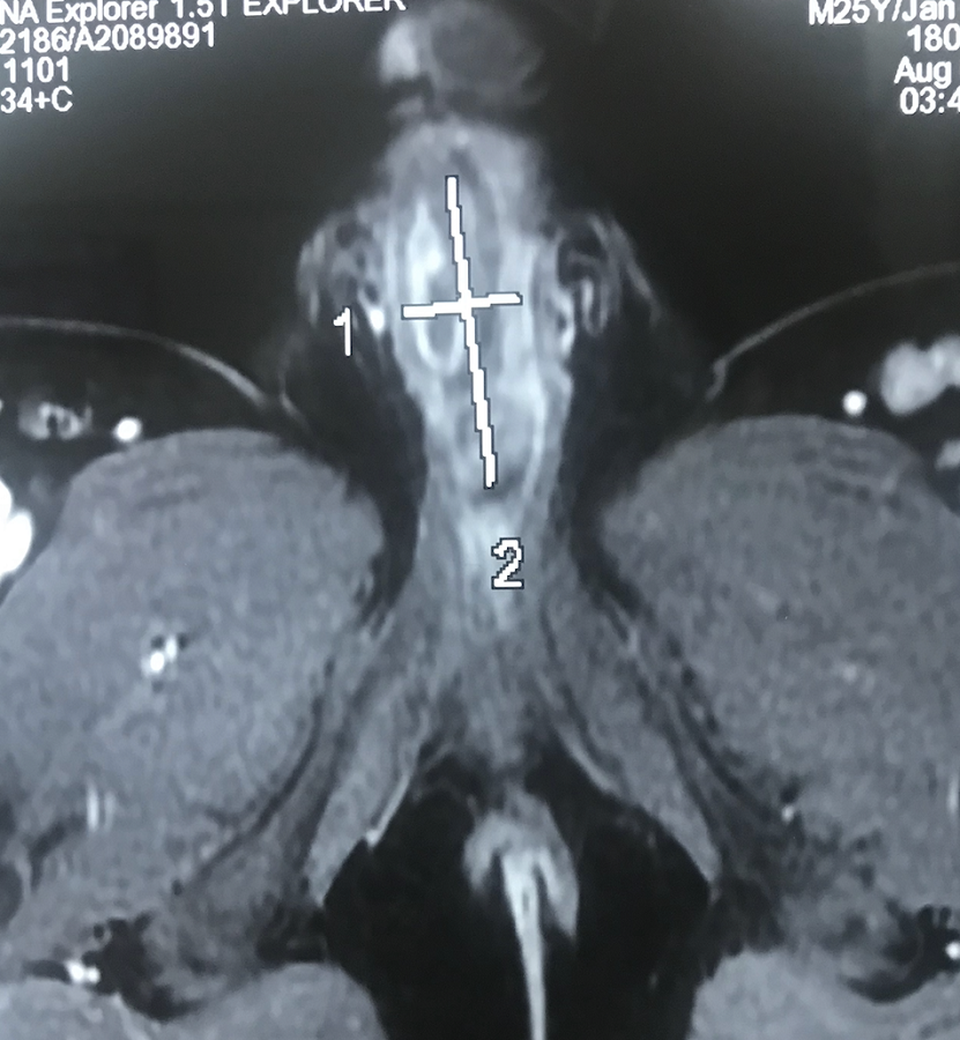

Các kết quả chẩn đoán hình ảnh bác sĩ phát hiện hình ảnh một vật lạ chưa rõ bản chất nằm trong niệu đạo. Để giải quyết nhanh chóng tình trạng bí tiểu và viêm nhiễm vùng sinh dục các bác sĩ tiến hành mở bàng quang ra da, chuyển lưu nước tiểu và điều trị kháng sinh nhẵm kiểm soát nhiễm trùng.

Khi tiến hành phẫu thuật thám sát và tái tạo đường tiểu mới cho người bệnh, ê kíp phát hiện một vật lạ đã ăn sâu, xuyên qua thành niệu đạo đến sát vách thể hang của dương vật. Ngay lập tức cuộc mổ được chuyển hướng tập trưng lấy dị vật. Các bác sĩ đã gắp ra khỏi niệu đạo một đoạn dây cước bị đóng sỏi xung quanh thành khối có kích thước khoảng 2,5cm x 6cm.